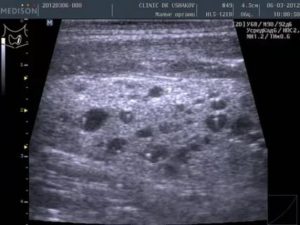

Множественные кисты

Множественные новообразования – не диагноз, а заключение ультразвукового обследования щитовидной железы. Термин употребляется по отношению к кистам, которые образуются сразу в обеих долях щитовидки. Симптом указывает на:

- Ультразвуковое обследование. При проведении УЗИ определяют диаметр, структуру уплотнений, отличают кисту в щитовидных долях от аденомы, струмы, аденокарциномы.

На первоначальном визите к эндокринологу, врач выясняет симптомы и проводит пальпацию. Определив наличие образования пальпаторно, врач направляет пациента на дифференциальную диагностику – УЗИ щитовидки. С помощью этого исследования определяется размер, структура и прочие характеристики новообразования.